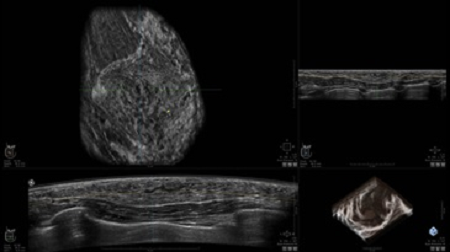

GE INVENIA ABUS – это современный УЗИ аппарат, который создан для точной и эффективной диагностики сканирования с высокой плотностью молочных желез. Выявляемость патологий раковых и предраковых стадий заболевания составляет 55%, что в конечном счете позволяет ставить врачу точные и своевременные диагнозы. Традиционные методы использования маммографии не показывают такой выявляемости, ограничиваясь лишь 3-38%.

УЗИ-аппарат GE INVENIA ABUS позволяет проводить максимально операторонезависимые процедуры, что значительно снижает риск неправильной постановки диагноза и сопутствующие издержки на обработку информации. Система готовит отчет в течение 3-х минут после сканирования, это безусловное преимущество по сравнению с обычным УЗИ сканером.

• датчик с изогнутой апертурой для качественного исследования

• сканирование одной грудной железы в трех проекциях не более 60 сек.;

• обработка результатов за три минуты.

• Получение объемных 3D изображений с возможностью покадрового просмотра

• Получение изображений в поперечной плоскости (в реальном времени) и в коронарной плоскости (статическая, для указания нахождения соска)

• Отображение объемных 3D ультразвуковых изображений, которые состоят из традиционных поперечных и воссозданных коронарных и сагиттальных проекций

• Стандартизованная ориентация изображения: «толстый срез» в коронарной плоскости; поперечная; сагиттальная плоскость; радиальный и антирадиальный поворот изображения; просмотр исключительно области интереса